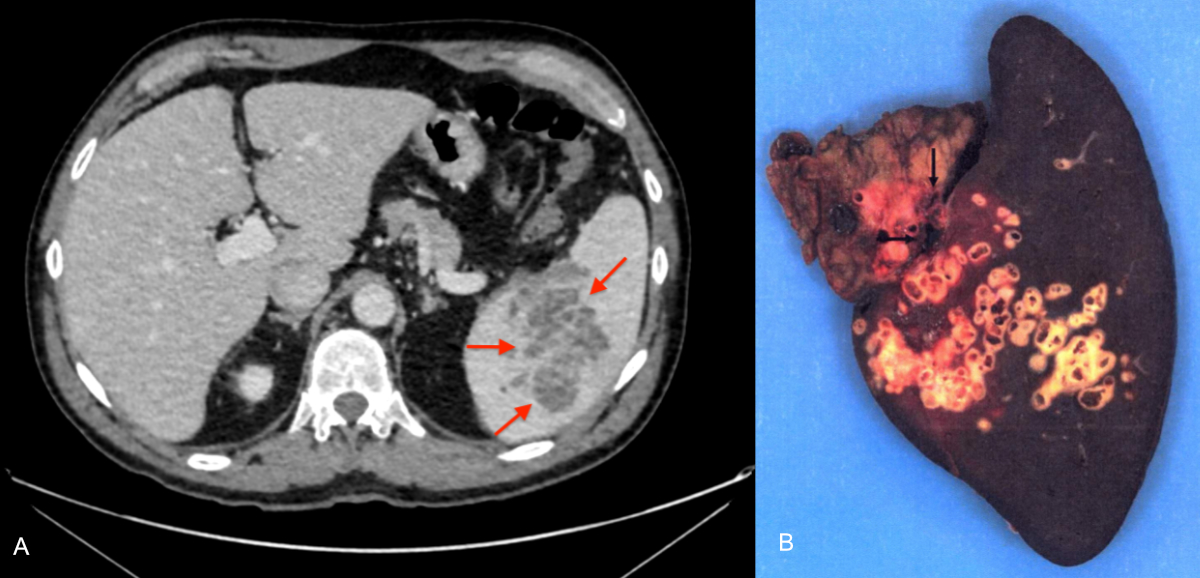

Figure 5A–B: 67-year-old patient admitted to the emergency department for a painful crisis in the left hypochondrium occurring 4 years after superior mesenteric vein thrombosis. A: Contrast-enhanced CT scan, portal phase, axial cut. Multicystic hypodense splenic lesion (arrows). B: Total splenectomy specimen, macroscopic view. The lesion is filled with multiple alveoli (arrows) characteristic of alveolar echinococcosis, corresponding to parasitic microcysts. No clear limits.

We report only one primary extrahepatic form (4%) as a splenic location. This result is consistent with those of a large European series (n = 599) [30] and a French series (n = 387) [25], reporting respectively 2% and 4% primary extrahepatic locations, including the spleen. The patient described in our series had a history of superior mesenteric vein thrombosis following laparoscopic resection of the caecum performed 4 years before the diagnosis of splenic alveolar echinococcosis. The mesenteric venous thrombosis likely facilitated redirection of blood flow towards the splenic vein, thereby allowing the primary infection of the spleen by the parasite. A case of primary vertebral alveolar echinococcosis in a patient with liver cirrhosis complicated by portal hypertension has recently been reported, probably involving the same mechanism of portal flow diversion [31].